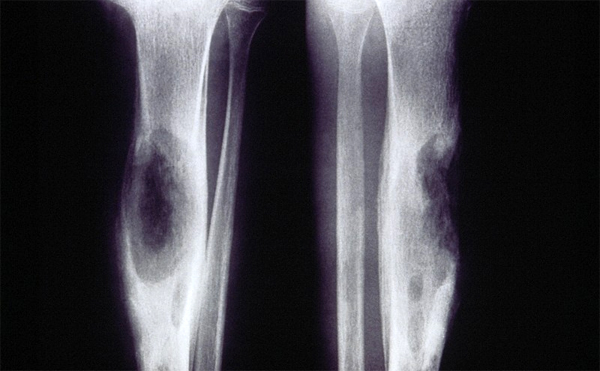

Рентгеновские снимки доброкачественных опухолей костей